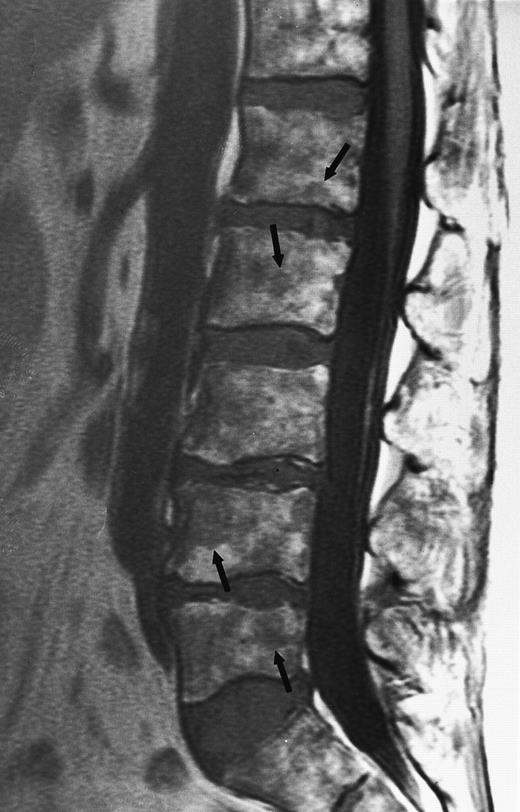

Lymphoma: multifocal bone marrow involvement. Sagittal T1-weighted (500/10, TR/TE) MR image of the lumbar spine shows multiple foci of bone marrow replacement (arrows). This appearance of lymphomatous involvement of the bone marrow is similar to bone metastases. Note extraosseous mass in the presacral space with apparent preservation of the bony cortex and small retroperitoneal lymph node at the level of L2 (arrowheads).